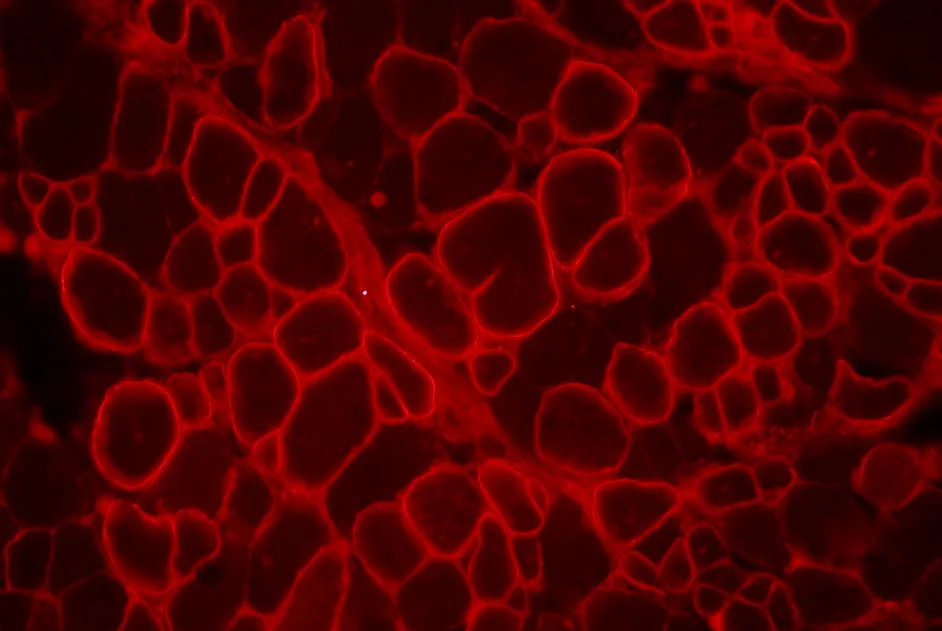

Maladie de Charcot-Marie-Tooth : implication du gène HADHB

Identification d’un nouveau gène à l’origine d’une forme axonale de maladie de Charcot-Marie-Tooth, le gène HADHB, qui code une protéine mitochondriale.